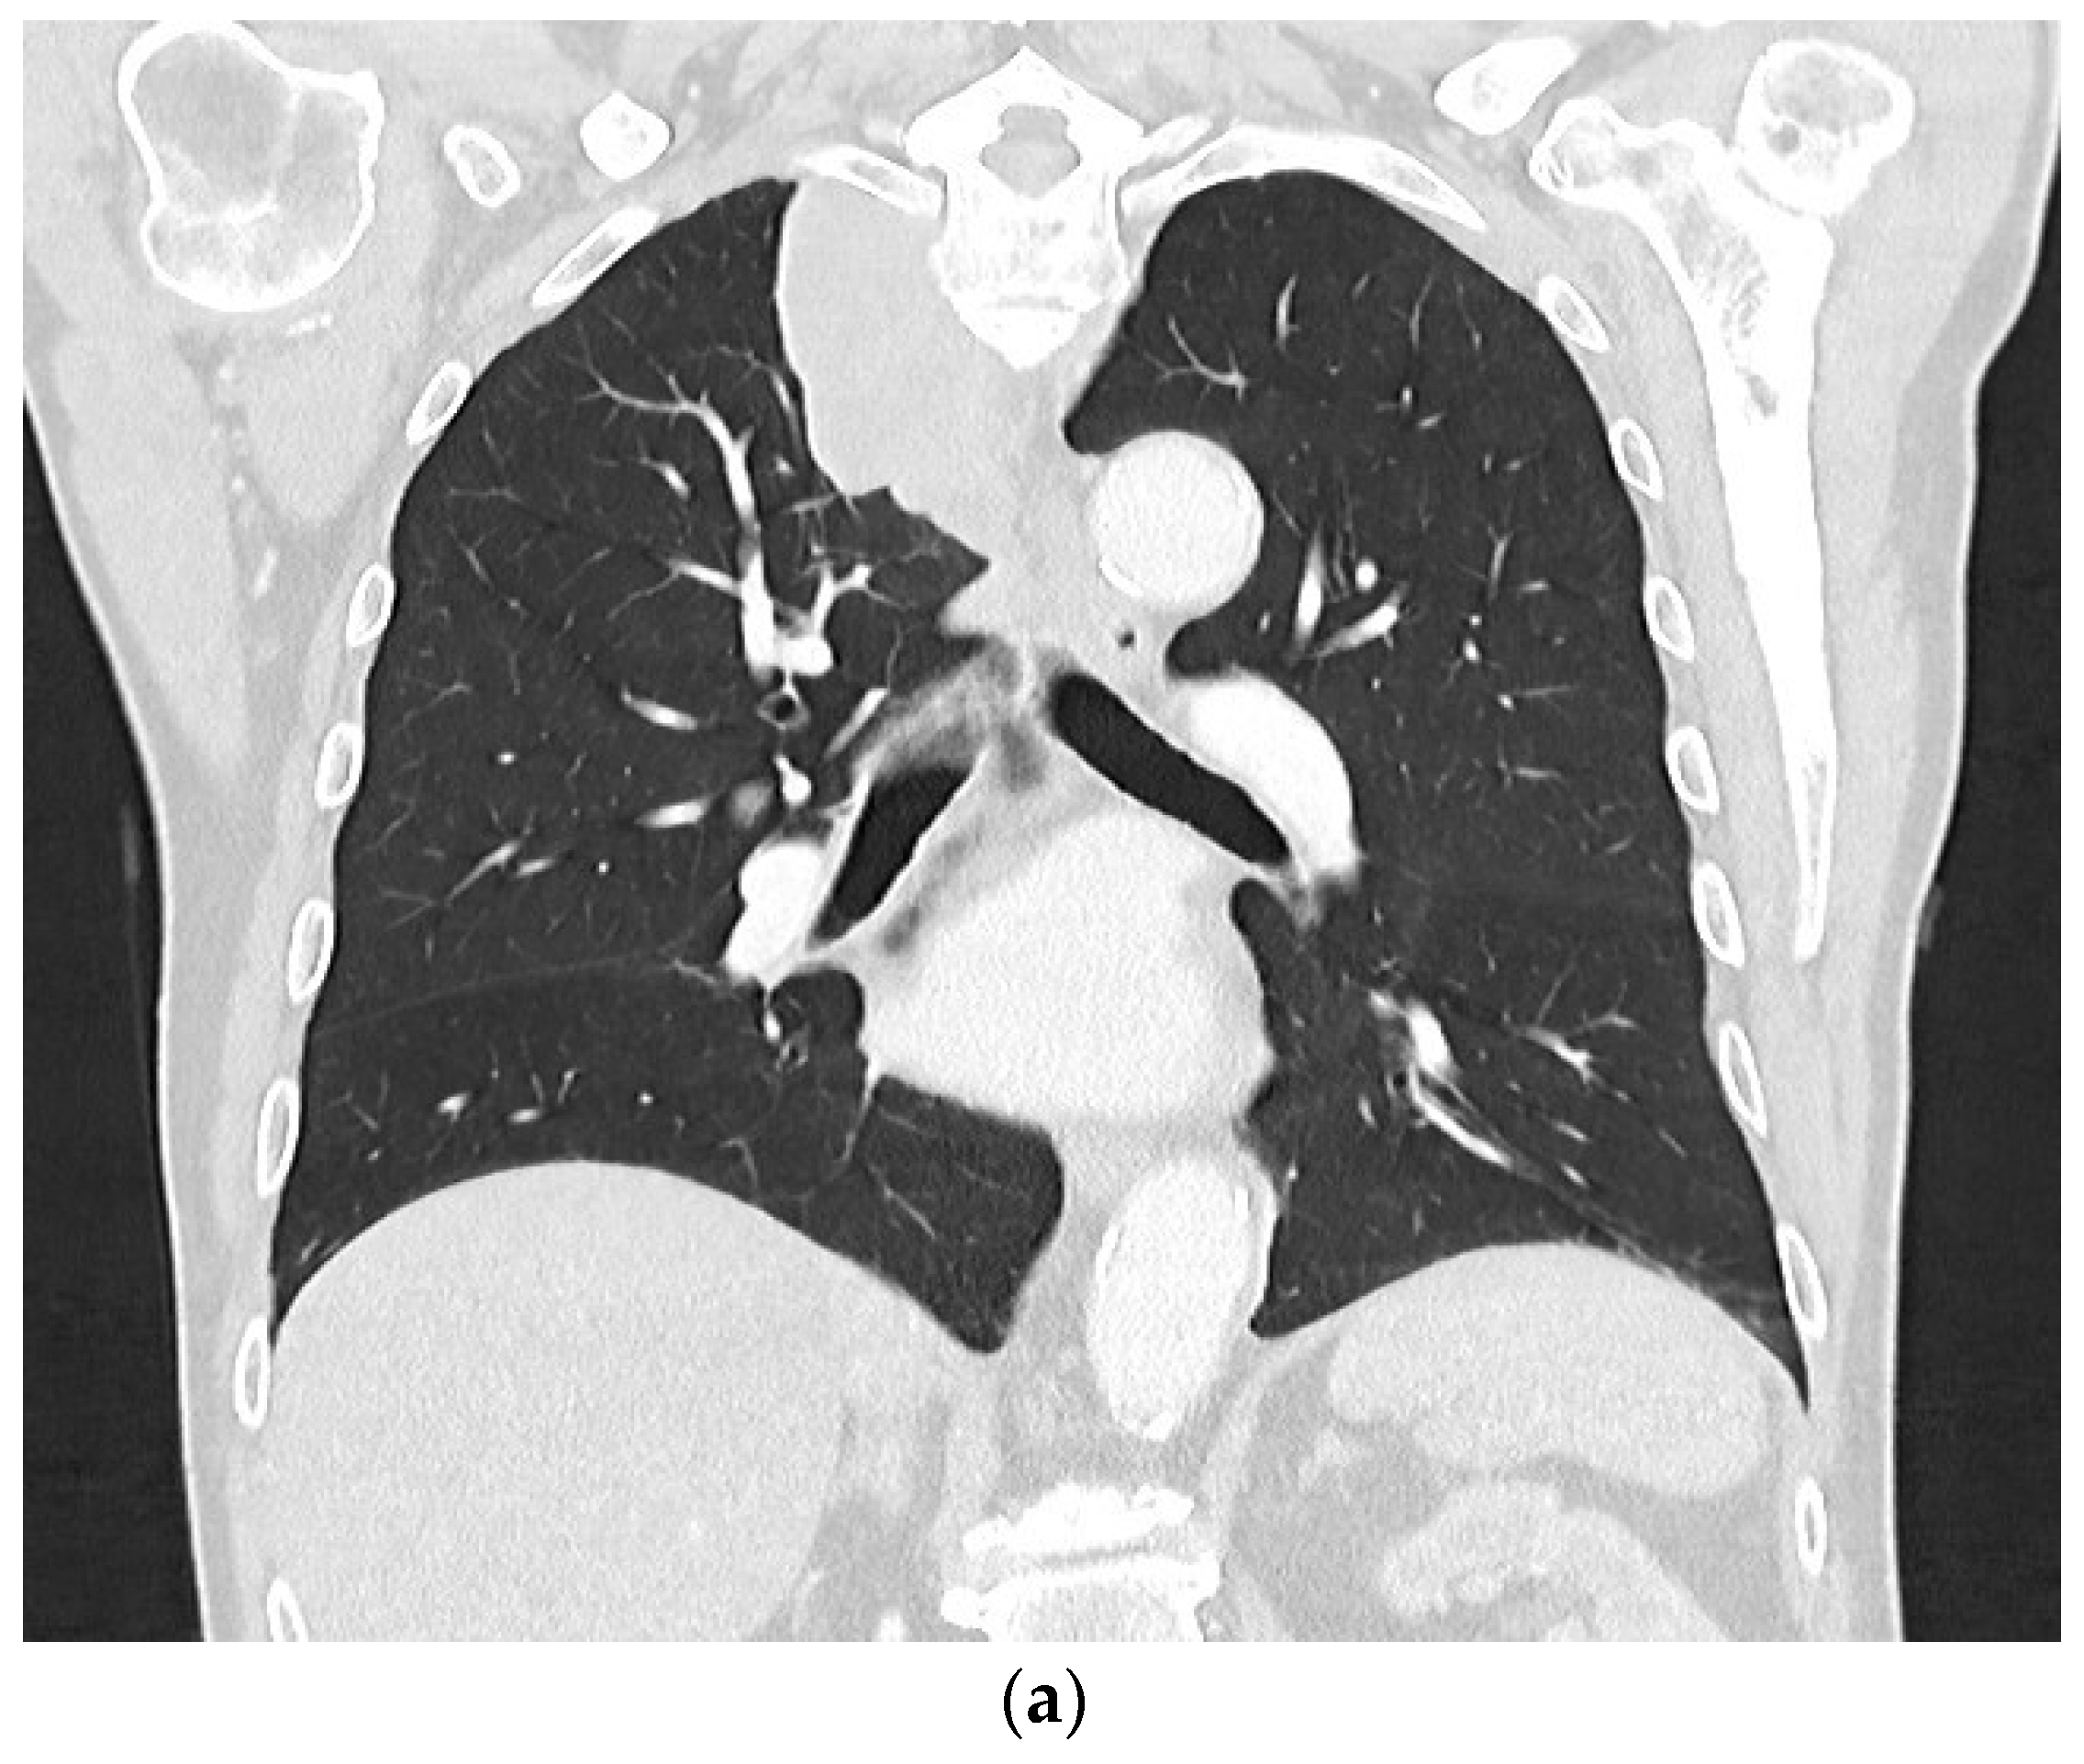

2. Primary Pulmonary Sarcomas